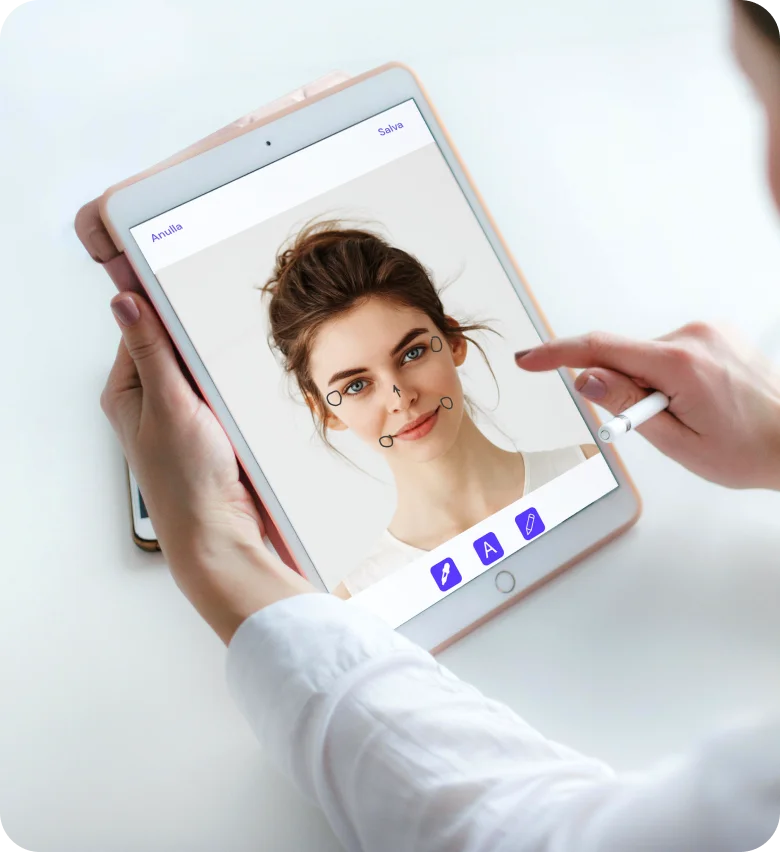

Gestisci facilmente tutti i processi della tua clinica, affidandoti a strumenti digitali sviluppati dal punto di vista del medico, come una cartella clinica completa, fotografie e annotazioni, tracciabilità delle scorte, firma digitale e marketing di follow-up.